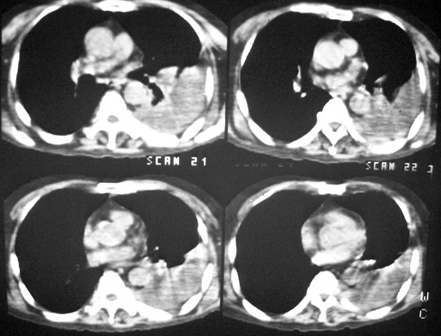

长年偏瘫卧床的病人,73岁,男。最近不能自理,饮食差,知觉不敏感,bp:140/80。脑ct是脑动脉硬化的表现,陈旧多发脑梗死。听诊左肺呼吸音低。行胸部ct扫描发现左侧大量胸腔积液,左侧肋骨虫蚀样破坏,请给予会诊一下:是否转移性病变还是其他?谢谢!

左侧后肋骨及椎弓骨质破坏,考虑转移瘤.降主动脉旁见一软组织块影,肿瘤与压迫之不张肺组织不能鉴别,建议增强扫描.

考虑;左侧周围性肺癌侵犯胸膜并肋骨转移.

考虑肋骨骨质破坏,病变肋骨皮质不连续,呈融骨样改变,不象骨质损伤后的修复样改变,未见到明显骨痂显示.软组织肿胀不明显,所以不太支持感染性破坏改变.

同意12楼分析,右肺癌侵及胸膜并肋骨转移。

肋骨骨质破坏!!中下部纵隔窗传上来看看!该不会有肺癌吧?纵隔内有淋巴结影。

左肺上叶尖后段实变、体积缩小,支气管开口后方似有一肿块,与胸壁、主动脉分界不清,局部肋骨呈混合型破坏,考虑肺癌肋骨、胸膜转移。

左侧包裹性胸腔积液,未见到明确的肿块影,纵隔窗伪影严重,纵隔可见到淋巴结(位于主动脉弓下)左侧肋骨病变是否与患者长年卧床有关

支持周围性肺癌伴肋骨胸膜转移.